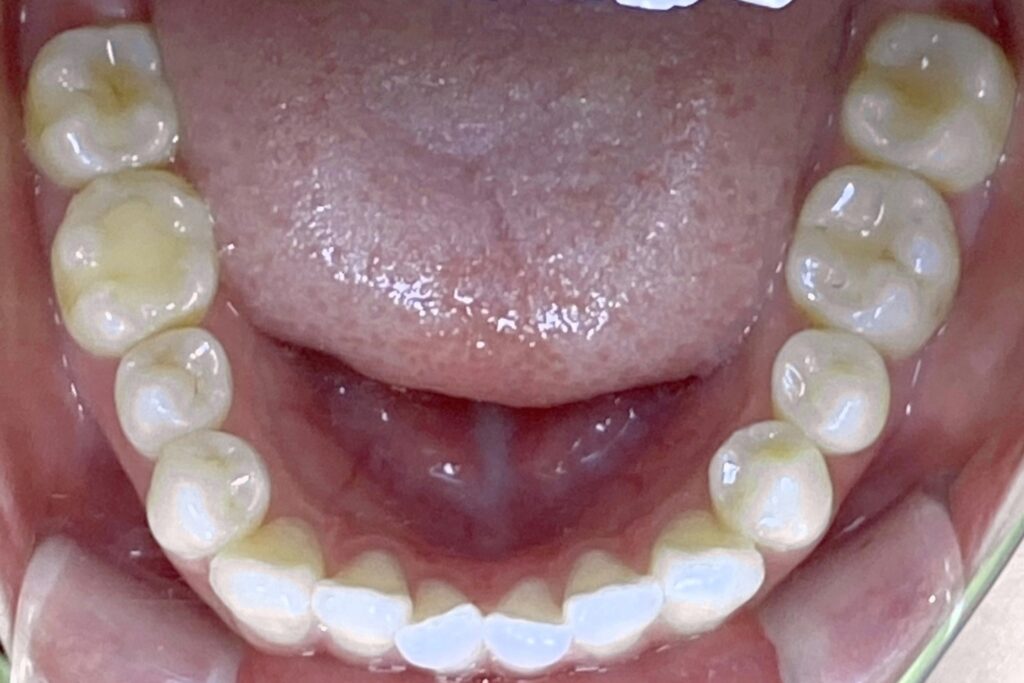

Before